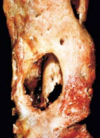

What is this joint showing?

- Fibrillation of cartilage.

- Eburnation of bone (polishing and grinding of bone on bone articulation)

- Sclerosis (bone below area of cartilage becomes more dense).

- Subcondral cyst: small fractures under eburnated bone –> joint fluid is forced into subarticular space –> fluid icites a host response and a fibrous capsule is made around it